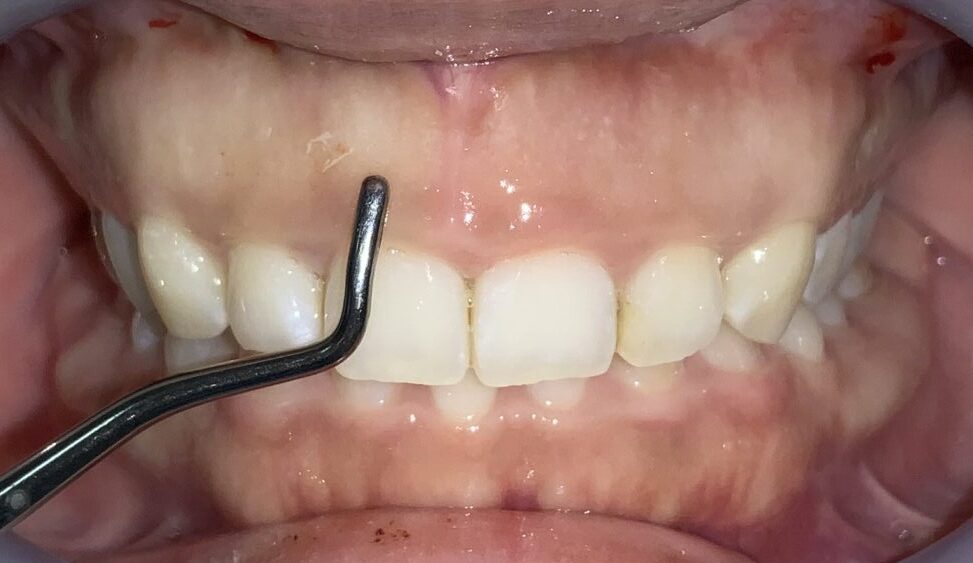

隣の歯も同じように検査します。

隣の歯は前歯ほどではないですが、しっかりと歯ぐきが、かぶっています。

この歯は犬歯です。犬歯もたくさんの歯ぐきに覆われているようですが、治療をする場合には注意が必要です。

犬歯はあまり大きくすると、八重歯のように見えてしまい、せっかくの治療が台無しになる場合があります。また、被っている歯ぐきがたくさんあっても、歯ぐきが薄い場合があり、このような歯ぐきの場合は、治療後に歯ぐきが退縮してしまい、歯槽膿漏の歯ぐきのように見えてしまう場合があります。